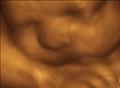

Our 3d 4d ultrasound studio provides you the opportunity for you and your family to see your baby suck its thumb and smile just like they will in your arms months from now. It's a memory that lasts.